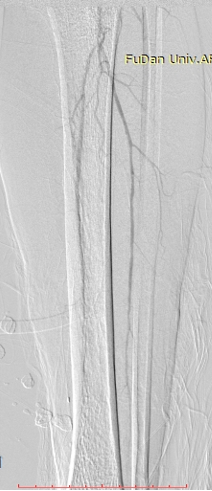

病例-2 男性,69岁,外院股腘动脉支架后再狭窄DCB后1年复发,右侧为重